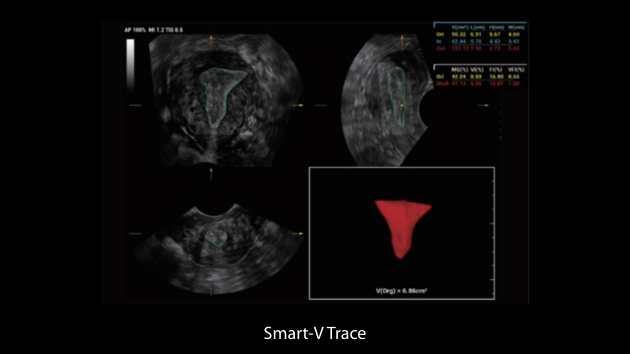

Clinical Images